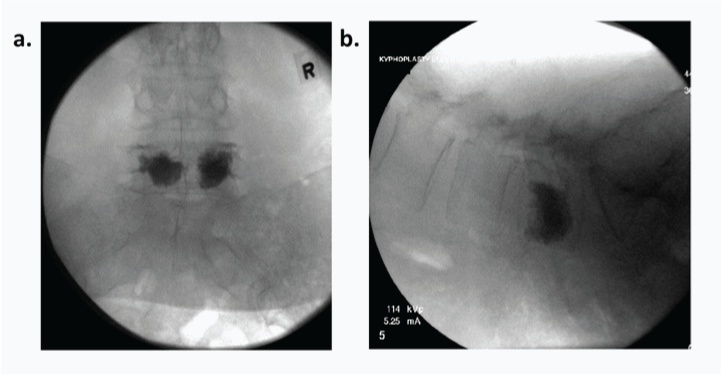

All patients in this study (n=81) were referred to the surgeon’s clinic. Visual analog scale (VAS) questionnaires (painscale from 1-10) were given preoperatively and postoperatively in the clinic at subsequent visits up to a year. Patients were consented to the procedure only after understanding the risks and benefits to the procedure. All procedures were performed in the hospital operating room. Patients were placed in the prone position. With intra-operative bi-planar fluoroscopy (Figure 1), the procedure was performed as described in the technique guide. All kyphoplasties were performing using Kyphon Balloon Kyphoplasty (Medtronic, Memphis, TN). Patients were sent home the same day if no complications occurred. Postoperatively, patients were not braced and had no physical restrictions. Patients were seen in clinic after the procedure at least twice within the first year. Spine anterior-posterior and lateral radiographs of the appropriate level(s) were obtained preoperatively and at each clinic visit. One year after the end of data collection period, patients were called to obtain short-form health survey (SF-36) scores. The questionnaires were performed over the phone and with either the patient or a family member’s assistance, all questions were completed. All data were collected only after Institutional Review Board approval was obtained from our institution. Demographics, clinical and radiographic outcomes, and risk factors for new fractures and other complications were analyzed. Data analysis was performed using SPSS (Chicago, IL) utilizing student’s t-tests.

Figure 1 AP (A) and lateral (B) intra-operative fluoroscopic images of L5 kyphoplasty. (Case performed by Fernando Techy, M.D. at Advocate Lutheran General Hospital, Park Ridge, IL).